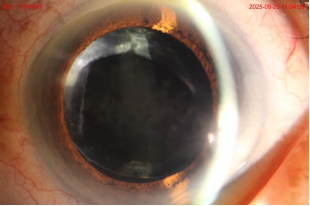

患者出現(xiàn)手術(shù)前一樣的視力模糊感,這種病稱為“后發(fā)障”。從術(shù)后數(shù)月至數(shù)年均有可能發(fā)生。目前,YAG激光晶體后囊膜切開術(shù)可以把晶體的囊膜,即那層模糊的膜,打一個4-5mm的圓孔,去除模糊的囊膜,讓視力變得清晰。

理想情況下視力可恢復(fù)到白內(nèi)障術(shù)后視力。不過,激光術(shù)后需要注意,一個月內(nèi)會出現(xiàn)漂浮物,這是正常現(xiàn)象,不要揉眼;避免劇烈運動,防止碰撞術(shù)眼。